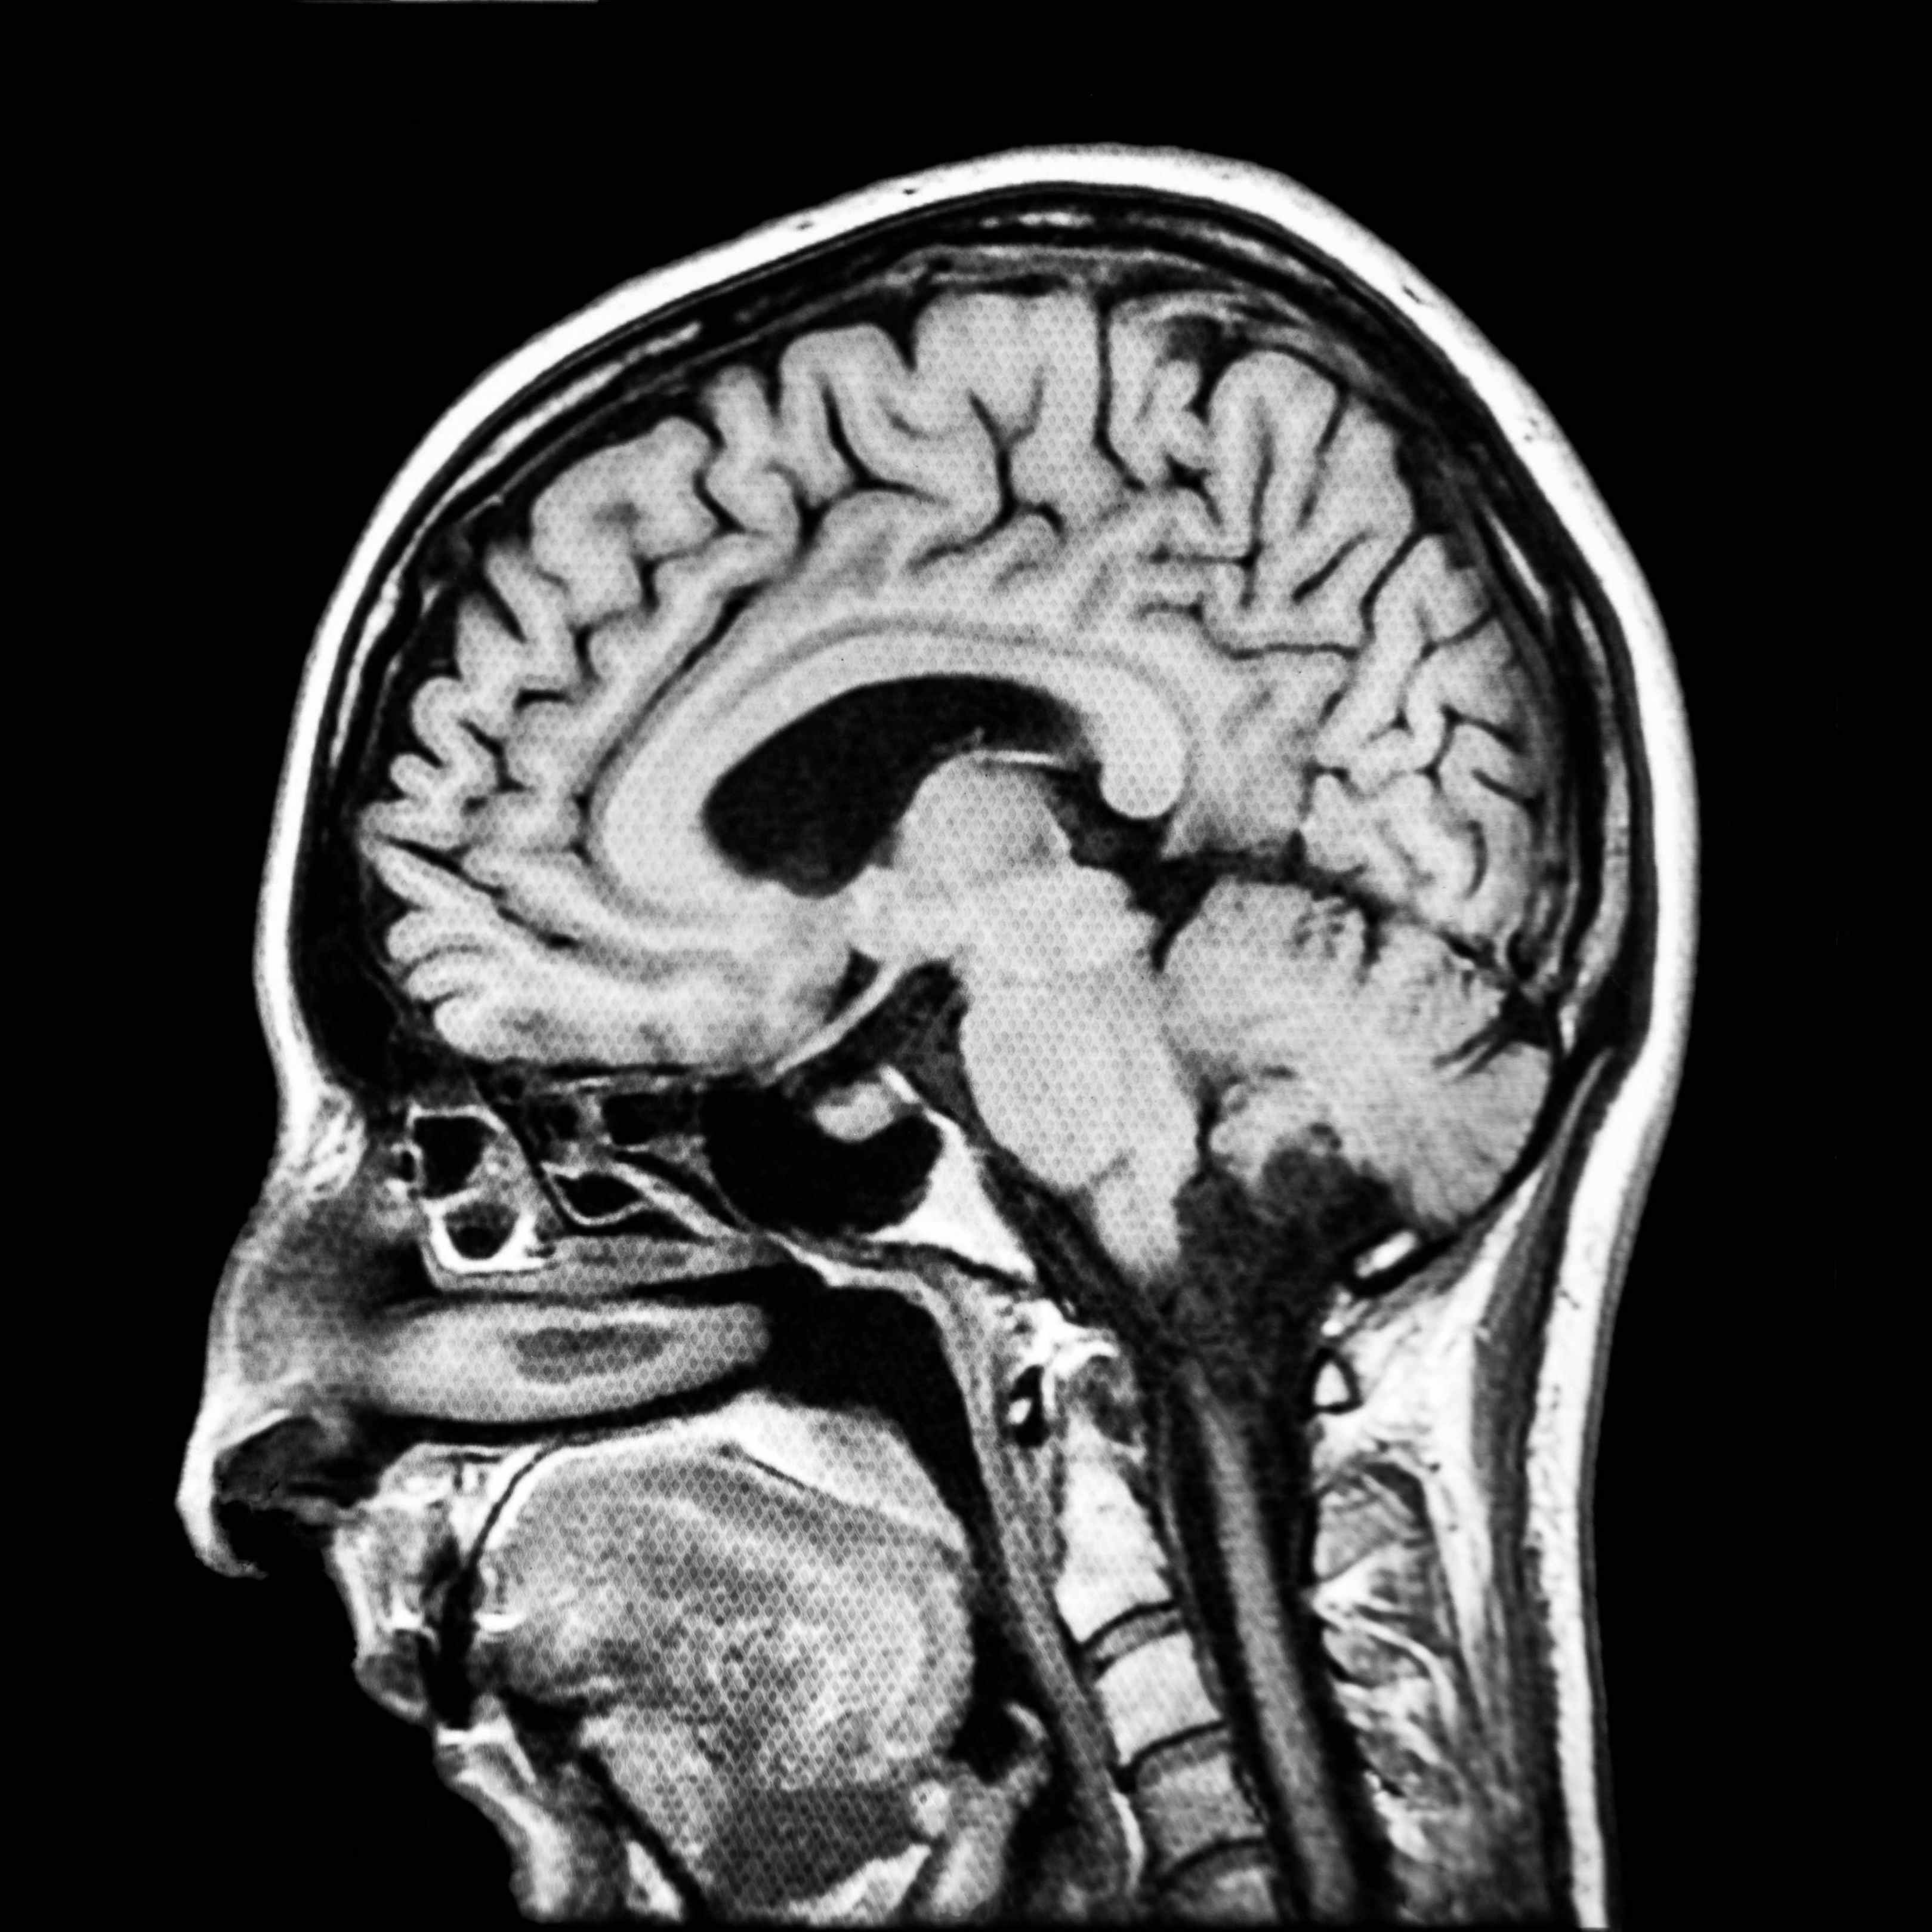

脑瘤是神经外科最常见的疾病。脑肿瘤的发病非常突然,往往令患者及家人猝不及防,女子手脚五官变形竟是脑部长瘤,在现实生活中,脑肿瘤一般都是缓慢侵润性生长,有很多早期症状容易被患者忽视。

而就在前几日,李女士因血压、血糖出现异常而到医院检查,结果才发现自己脑部出现一种特殊的脑肿瘤----“生长激素型垂体腺瘤”。